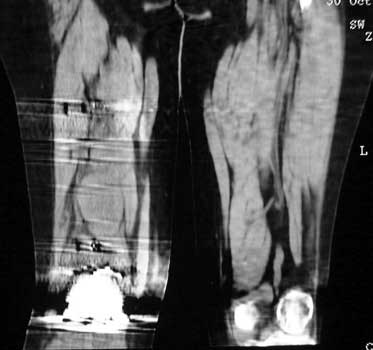

Mass in patient with modular endoprosthesis placed after resection of femur for osteosarcoma. Axial (fig A) and coronal reformatted images (fig B) clearly demonstrate mass adjacent to modular endoprosthesis. 14 gauge core needle biopsy performed under CT guidance (fig C) demonstrated recurrent osteosarcoma